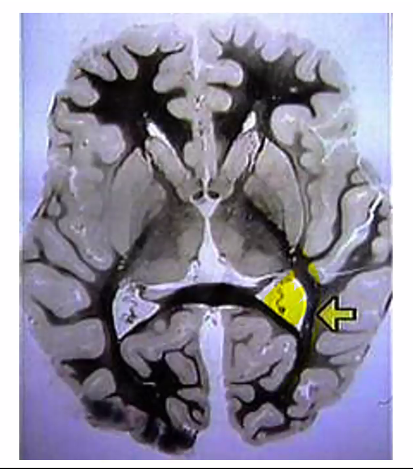

Parahippocampal Uncus Definition

The uncus is the medial, anterior part of the parahippocampal gyrus in the temporal lobe, and it contains part of the primary olfactory cortex (piriform cortex + amygdala connections).